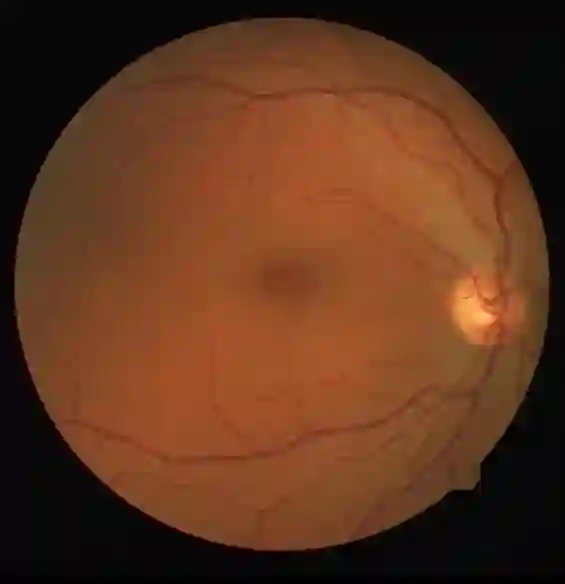

Retinal artery/vein (A/V) classification is a critical technique for diagnosing diabetes and cardiovascular diseases. Although deep learning based methods achieve impressive results in A/V classification, their performances usually degrade severely when being directly applied to another database, due to the domain shift, e.g., caused by the variations in imaging protocols. In this paper, we propose a novel vessel-mixing based consistency regularization framework, for cross-domain learning in retinal A/V classification. Specially, to alleviate the severe bias to source domain, based on the label smooth prior, the model is regularized to give consistent predictions for unlabeled target-domain inputs that are under perturbation. This consistency regularization implicitly introduces a mechanism where the model and the perturbation is opponent to each other, where the model is pushed to be robust enough to cope with the perturbation. Thus, we investigate a more difficult opponent to further inspire the robustness of model, in the scenario of retinal A/V, called vessel-mixing perturbation. Specially, it effectively disturbs the fundus images especially the vessel structures by mixing two images regionally. We conduct extensive experiments on cross-domain A/V classification using four public datasets, which are collected by diverse institutions and imaging devices. The results demonstrate that our method achieves the state-of-the-art cross-domain performance, which is also close to the upper bound obtained by fully supervised learning on target domain.